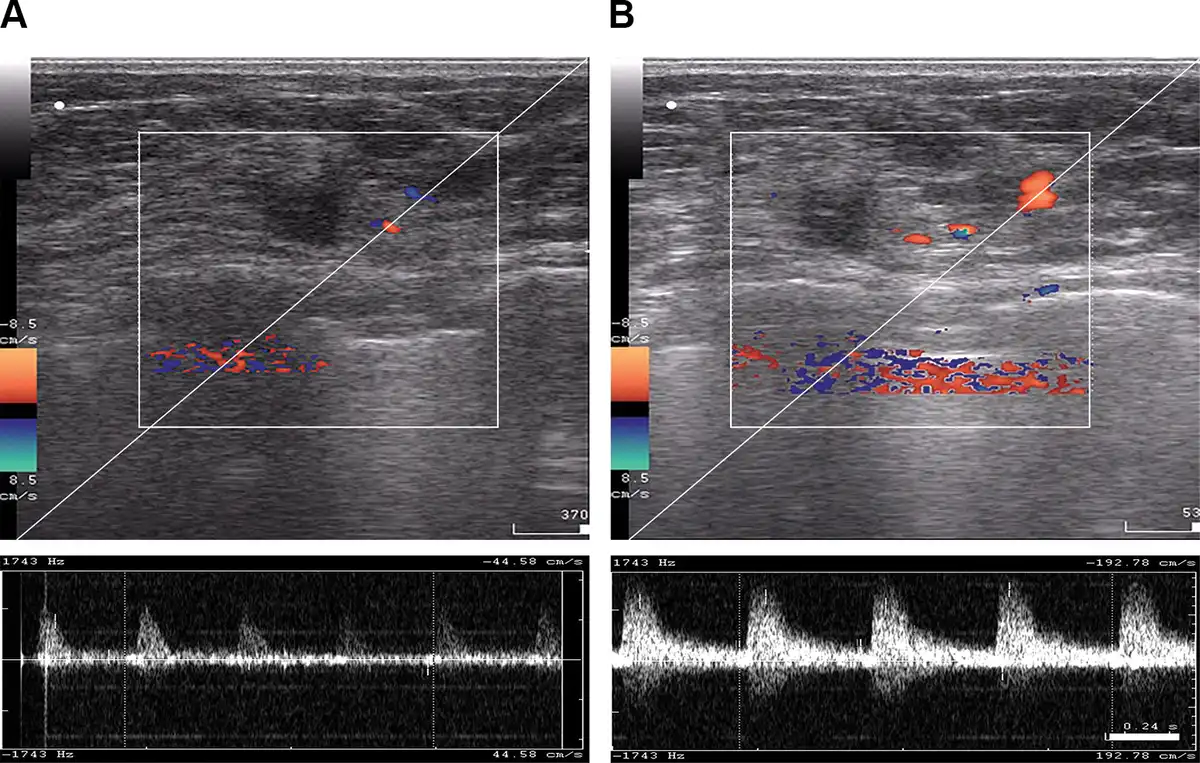

Figure 5

B-mode and color Doppler ultrasound imaging of tumor blood flow acquired from a patient with locally advanced breast cancer before regional inductive moderate hyperthermia (A) and 30 minutes after (B) treatment.

Color Doppler US examinations were recorded to assess blood flow in the breasts in the experimental group (Figure 5). RIMH significantly increased the number of color signals detected through the blood vessels in the breast tissue. The blood flow rate increased from 44.58 cm/s to 192.78 cm/s after treatment. The mean values for systolic blood flow were 3.5 times as high as those prior to the RIMH session. Similarly, the mean diastolic blood flow tended to raise after RIMH. Doppler signals from tumor vasculature were more variable due to spatio-temporal heterogeneity of breast tumors.